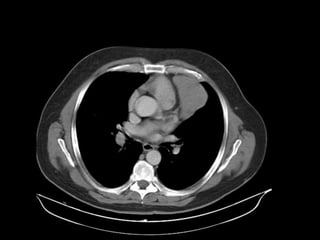

TOMOGRAFIA

RADIOGRAFIA • Radiografía normal •Radiografía patológica – Ensanchamiento mediastinal • Técnica radiográfica • Estructuras normales de tamaño o distribución atípica • Estructuras vasculares • Tumores